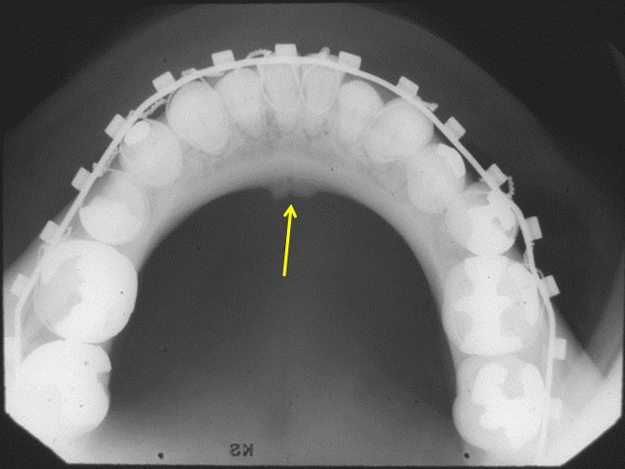

incisive canal

passageway thru bone that extends from superior foramina from incisive canal to foramen

tubelike radiolucent area with radiopaque borders, can be seen intraoral img

what is this, its description and its appearance on images

incisive foramen

hole in bone located at midline of anterior hard palate directly posterior to maxillary central incisors

round radiolucency located btween roots of maxillary central incisors, can be seen intraoral img